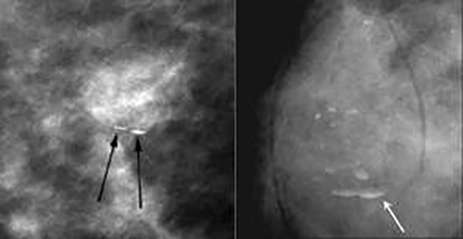

![]() Skin calcifications: often polygonal calcifications with radiolucent center

![]() Vascular calcifications: parallel calcifications outlining the vessel wall